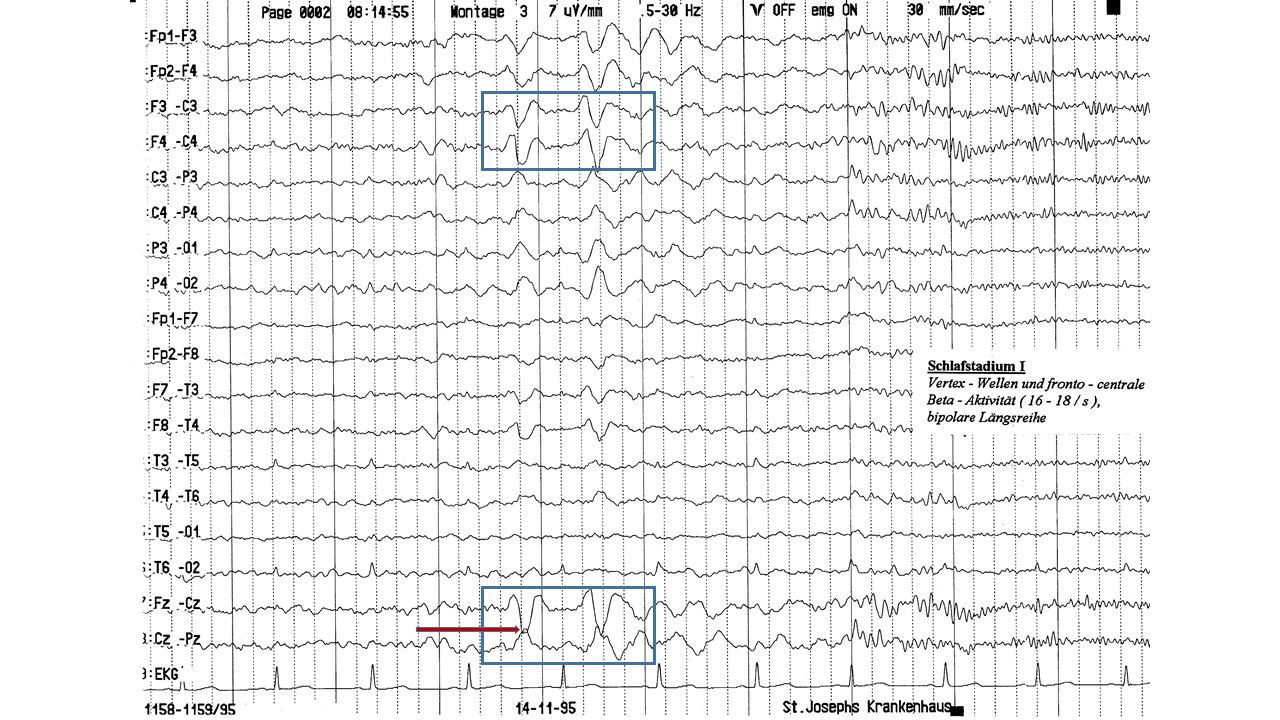

folie625.jpg